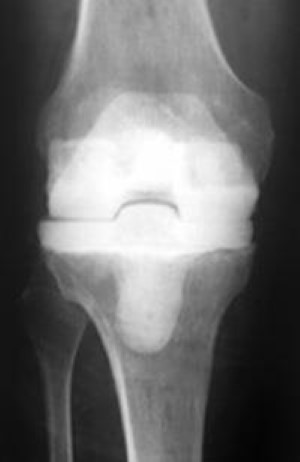

loose implant caused by osteolysis

Osteolysis (red arrow) has occurred around the tibial component, causing it to become loosened from the bone (blue arrow).